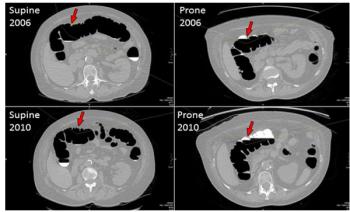

Case History: Female patient in early 60s with abdominal pain and nausea.

Using an algorithm with CT colonography allows radiologists to recognize previously identified polyps.